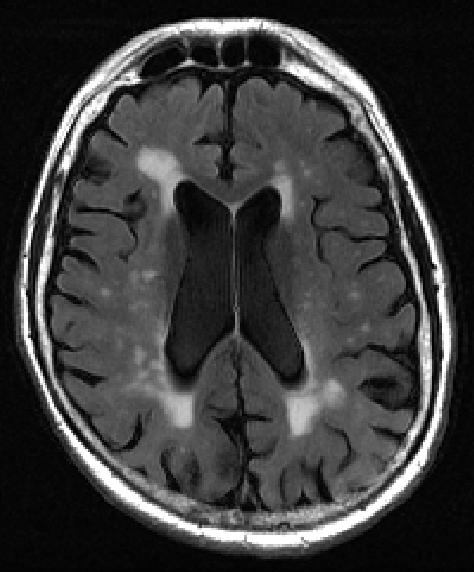

image: Caption: MRI image of human brain shows multiple bright spots (white matter hyperintensities) in center

The findings by imaging specialists at NYU Grossman School of Medicine center on small bright spots on scans called white matter hyperintensities. Increased numbers and size of the intense-white spots seen on the mostly gray images of the brain have long been linked to memory loss and emotional problems, especially as people age.

More spots on MRI and their occurrence in the center of the brain have also been shown to correlate with the worsening of dementia and other brain-damaging conditions, such as stroke and depression, say the study authors. The spots represent fluid-filled holes in the brain, lesions that are believed to develop from the breakdown of blood vessels that nourish nerve cells.